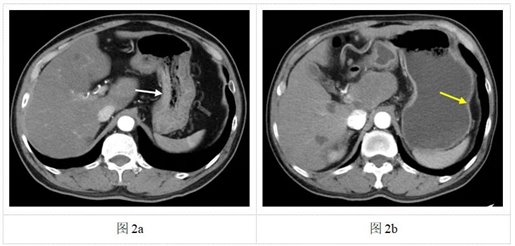

图2a:第一次检查时患者未喝水,胃腔没有充盈,胃壁显得较厚(白色箭头)。此时若存在小溃疡或早期胃癌等病变(藏在厚厚的胃壁里),很容易被漏掉。图2b:第二次检查时患者充分饮水,胃腔被撑开,胃壁变薄(黄色箭头)。此时若有异常增厚(比如肿瘤或炎症),就能更清楚地被发现。